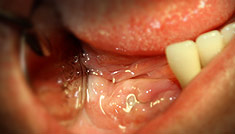

An implant is made of a titanium alloy inserted in the jaw bone for replacement of the root of the tooth. A dental prosthetic (crown) installed on an implant has an ideal form and natural color and looks as real as a natural tooth.

Installing implants is a standard dental procedure. Installation of an implant takes about 20 minutes. During the installation normal anesthesia is used, which makes the procedure completely painless.

Gums may remain sensitive for several days after the procedure, but will not bleed. Most patients stop taking painkillers the next day after the installation.